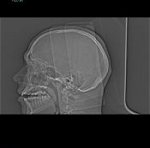

Röntgenaufnahme meines Schädelprofils |